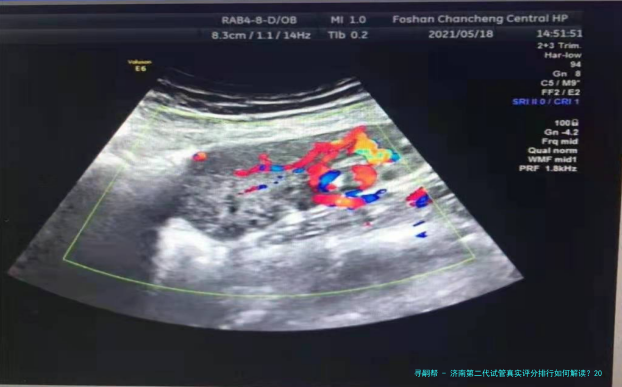

选择第二代试管(ICSI)医院时,单精子注射技术的成熟程度与胚胎培育试验室等级直接影响性价比。下列是济南地区主流医院的综合数据相比较:

第二代试管费用高于代,因增加了单精子注射环节。2025年济南地区样板费用构成如下: